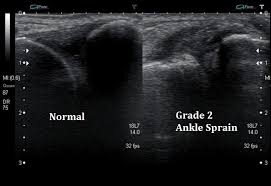

단순염좌, 부분파열, 완전파열 등을

인대 손상을

정확하게 체크하려면

아래 그림처럼

실시간 초음파 검사나

MRI로 봐야합니다.

좌측: 정상 인대 / 우측: 손상된 인대

좌측 정상에 비해서

우측의 인대는

급성 염좌로 많이 붓고

어둡게 보입니다.